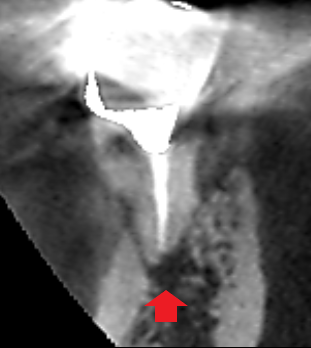

精密根管治療6カ月後の経過観察時の矢状断のCT画像です。下顎第一大臼歯の近心根の根の先にあった膿の影が消失し歯槽骨が再生しています。